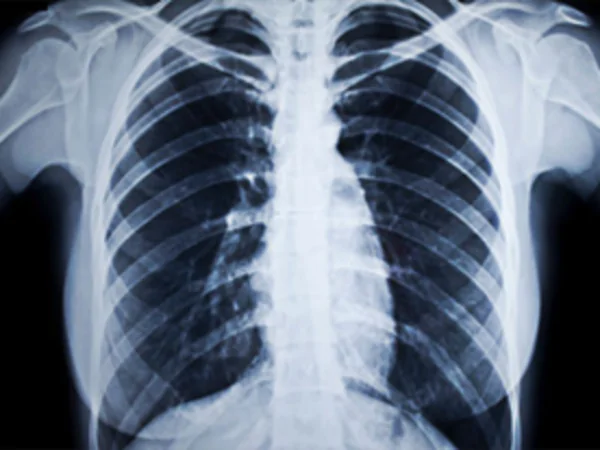

+ Y học: chụp hình, chiếu điện tử, chữa bệnh ung thư nông;

Ảnh chụp bằng tia X (X quang) giúp bác sĩ chẩn đoán chính xác bệnh lý.